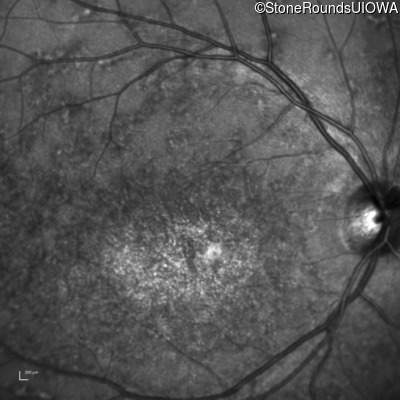

Infrared Fundus Photograph - Left - 20/200

Exemplar